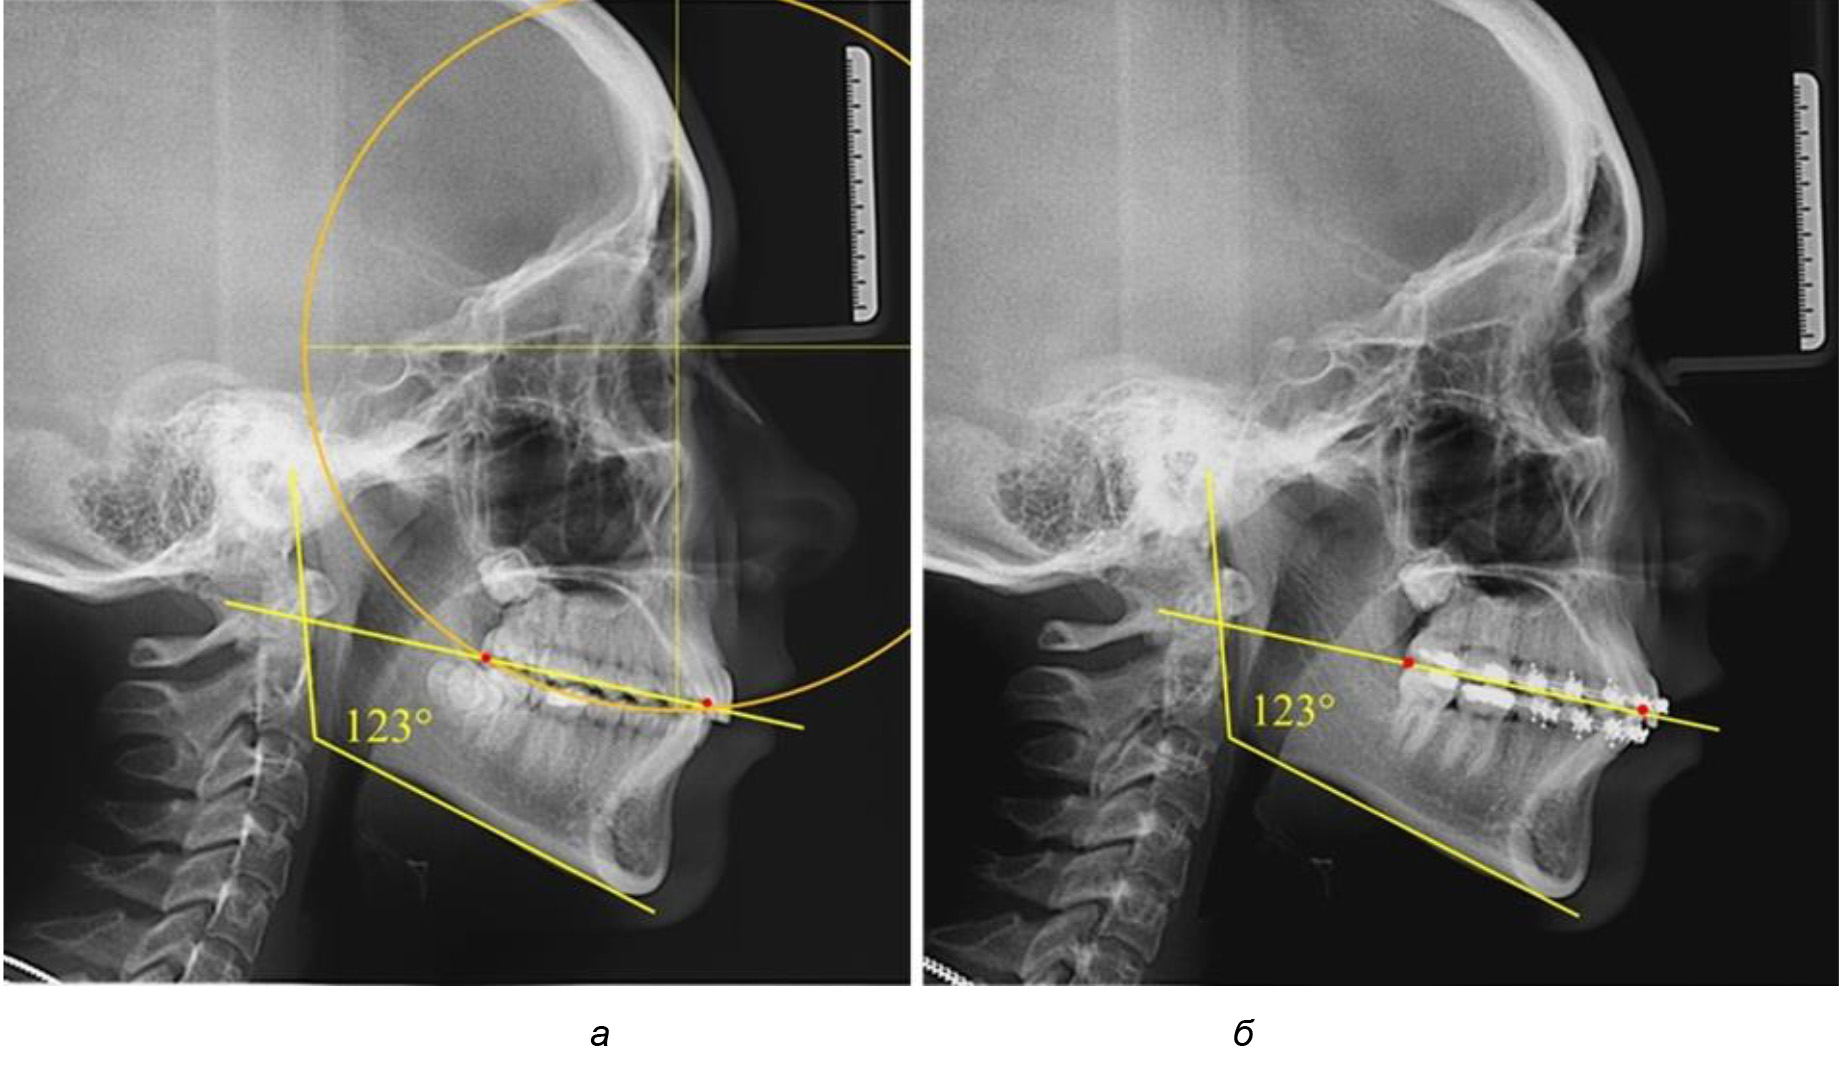

Глубина кривой Spee в среднем по 2-й подгруппе составила (5,69 ± 1,57) мм, что было достоверно больше, чем у людей с физиологической окклюзией (р ˂ 0,05). Достоверных различий с показателями, полученными при анализе ТРГ и ОПТГ, нами не отмечено (р ˃ 0,05). Отношение радиуса окружности к сагиттальному размеру окклюзионной линии в среднем по подгруппе составляло 1,372 ± 0,042 и не соответствовало числу Фибоначчи, что может быть использовано в качестве диагностического критерия определения патологической формы кривой Spee. После лечения пациентов техникой «прямой» дуги было отмечено незначительное увеличение сагиттального размера окклюзионной лини в среднем на (2,12 ± 0,77) мм. Однако окклюзионная линия практически касалась окклюзионного контура всех жевательных зубов, и отмечалось практически полное отсутствие кривой Spee.

Таким образом, проведенное лечение техникой «прямой» дуги способствует нормализации окклюзионного равновесия и торку передних зубов, однако не соответствует оптимальному окклюзионному статусу, характеризующему физиологическую окклюзию. При этом величина нижнечелюстного угла оставалась на прежнем уровне (рис. 5).

Рис. 5. Особенности ТРГ при патологической кривой Spee до лечения (а) и после лечения (б) техникой «прямой» дуги

После лечения пациентов техникой «прямой» дуги, так же как и в 1-й подгруппе, было отмечено увеличение сагиттального размера окклюзионной лини в среднем на (2,38 ± 0,83) мм. Окклюзионная линия практически касалась окклюзионного контура всех жевательных зубов, и отмечалось практически полное отсутствие кривой Spee, так же как и у людей 1-й подгруппы 2-й группы (рис. 6).

Рис. 6. Особенности ТРГ при оптимальной кривой Spee до лечения (а) и после лечения (б) техникой «прямой» дуги

Таким образом, проведенное лечение техникой «прямой» дуги способствует нормализации окклюзионного равновесия и торку передних зубов, однако не соответствует оптимальному окклюзионному статусу, характеризующему физиологическую окклюзию. При этом величина нижнечелюстного угла оставалась на прежнем уровне.